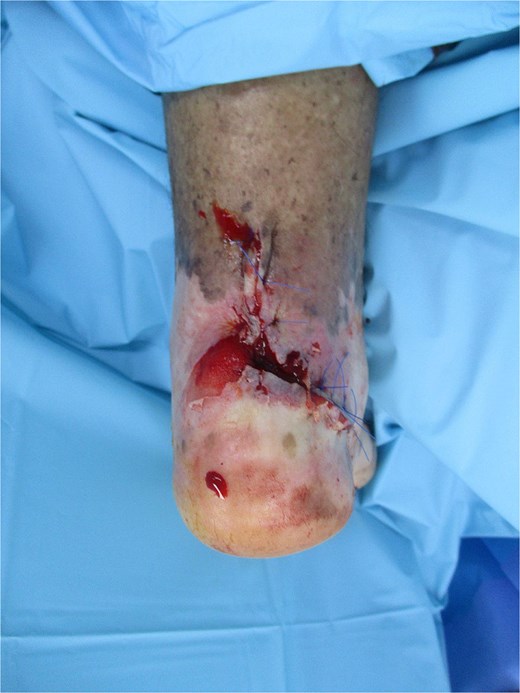

On general examination, the patient appeared well and oriented without fever. Vascular examination revealed non-palpable pedal pulses. Neurological examination revealed: protective and epicritic sensation were absent on both feet. Orthopedic examination: limited range of motion at the left ankle, with muscle strength preserved. On local examination: A full-thickness 3 × 2 cm ulcer with irregular borders, fibrotic and granulation tissue base, and keratotic crusted edges was located in the retrocalcaneal area. There were no signs of erythema, purulent discharge, foul odor, or exposed bone. However, elevated skin temperature was noted around the ulcer (Fig. 1).

Chronic non-healing retrocalcaneal ulcer at the initial presentation.